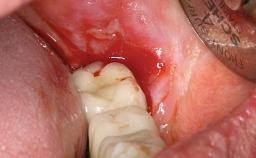

A 65-year-old female patient was referred to the periodontist for assessment and management of implant site 12. Implant 12 had been placed ten years previously and restored with a cemented single crown. The patient was a non-smoker in good general and periodontal health. On examination there were 7 mm probing depths at implant 12 with suppuration and bleeding on probing. The patient was aware of the presence of pus but had no discomfort. A periapical radiograph showed marginal bone loss to approximately the third thread of the implant. Previous radiographs obtained from the referring clinician indicated that there had been progressive bone loss since the implant was restored. A diagnosis of periimplantitis was made.